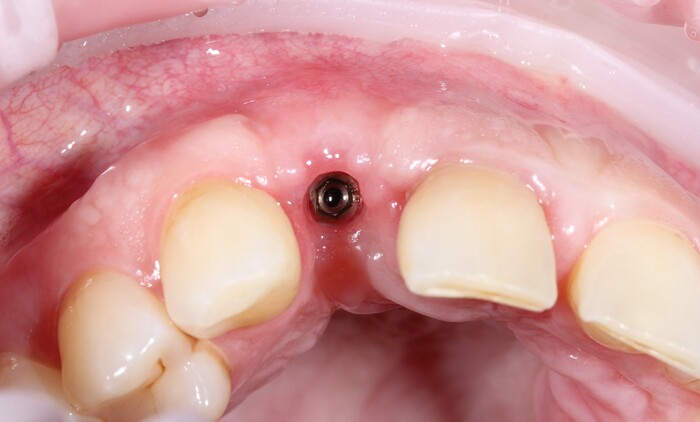

Но мне повезло, ко мне на прием пришла прекрасная девушка (а не усатый господин в плаще на голое тело) с ужасной, с ее слов, проблемой. Когда-то давно ей поставили имплантат в области верхнего бокового резца, но в связи с тем, что положение имплантата было неправильным, а одномоментно с имплантацией пластики десны не проводилось, последняя начала постепенно «подниматься», оголился абатмент (та часть, «за которую держится коронка»). Со слов пациентки, тем же доктором была предпринята попытка сделать пластику десны, не снимая этой коронки. Но, увы, развился некроз, что только усугубило ситуацию.

На момент моего осмотра это выглядело так:

Согласитесь, не особо эстетично. Ортопантомограмма: